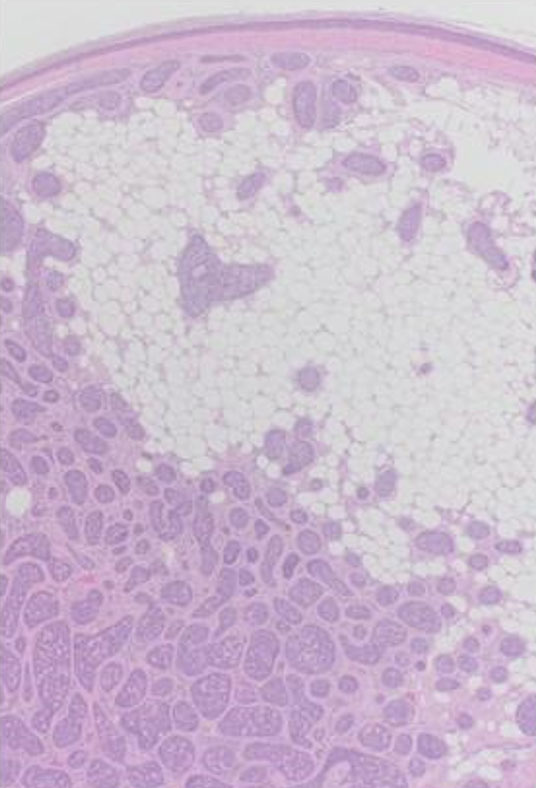

Microscopic examination showed a poorly circumscribed, unencapsulated dermal based tumor composed of multiple variably sized, irregularly shaped basaloid nests and islands of basaloid cells, separated and ensheathed by an eosinophilic hyalinized band like basement membrane, forming the characteristic “Jigsaw puzzle” like pattern of a cylindroma (Figure 1 and Figure 2). A band of compressed papillary dermis was appreciated separating the dermal based basaloid islands from the overlying epidermis, without any appreciable connection. The islands were composed of smaller, bland appearing basaloid cells with hyperchromatic nuclei mostly located at the periphery of the islands, with larger paler cells with vesicular shaped nuclei within the central areas. Focal duct like formations were seen, along with globules of brightly eosinophilic hyaline basement material within the islands. Near the periphery of the tumor, mature adipocytes were seen separating the dermal basaloid nests with surrounding eosinophilic bands, expanding the stroma between nests, distributed circumferentially up towards the papillary dermis (Figure 3 and Figure 4). No necrosis, nuclear atypia, or mitotic figures were identified.

Figure 1: Poorly circumscribed dermal based tumor with variably sized irregularly shaped basaloid nests/lobules. Band of compressed papillary dermis separates the islands from the overlying epidermis (H&E, 20×).

Figure 4: Mature adipocytes within the intervening stroma between the basaloid lobules, mostly distributed superficially and circumferentially around the islands in the reticular dermis towards the papillary dermis (H&E, 40×).